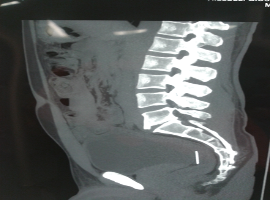

Citation: Gambardella D, Stelitano S, Capomolla A, et al. Unusual Noningested Intraperitoneal Needle as a Foreign Body: Laparoscopic Removal with Two Accesses. Clin Image Case Rep J. 2021; 3(2): 137.